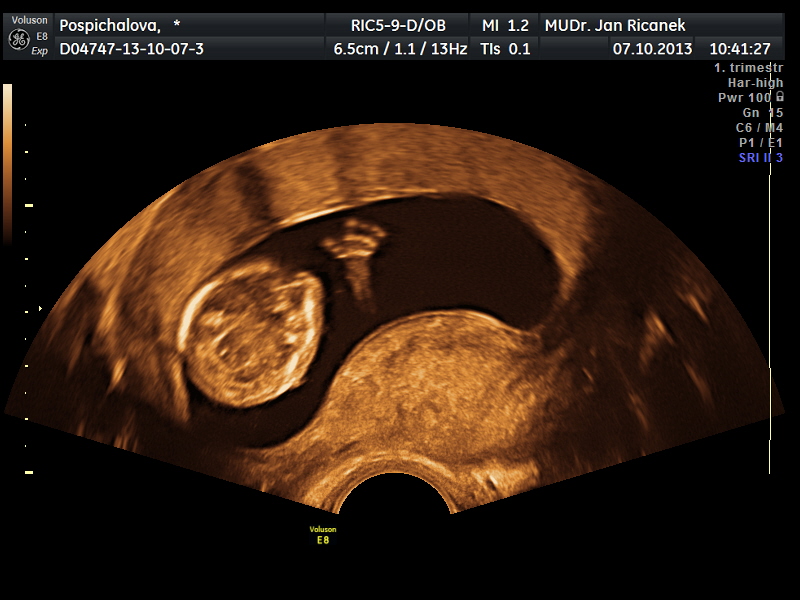

Miminko :)